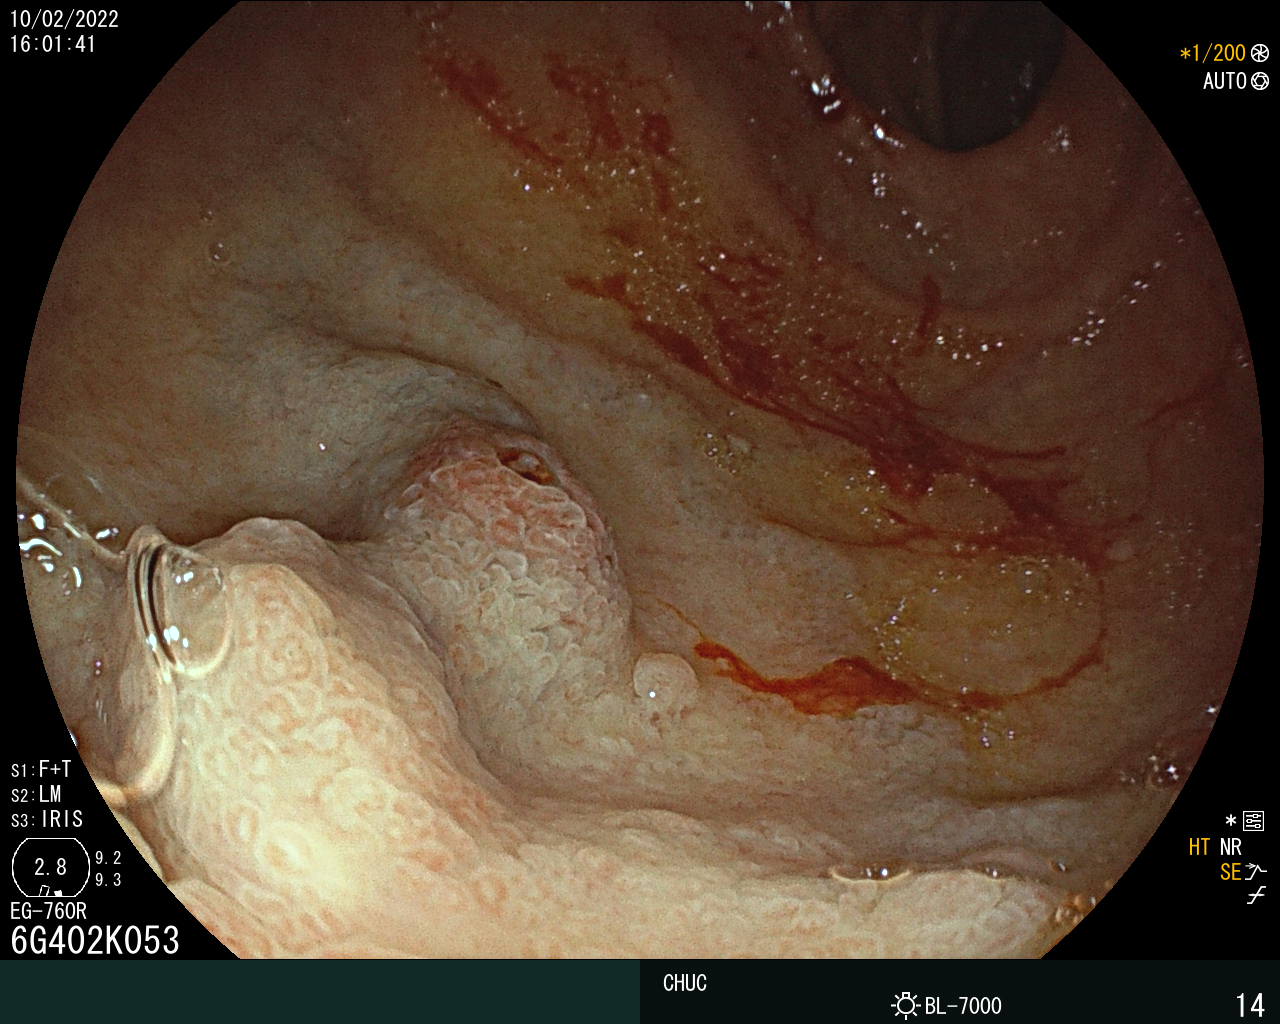

Duodenal varix as a presentation of hepatocellular carcinoma

André Coimbra Trigo, Mafalda João, Sandra Lopes, Pedro Figueiredo

Centro Hospitalar da Universidade de Coimbra

A 79-year-old man with alcoholic liver cirrhosis presented with hematemesis. An upper endoscopy revealed a varix at the anterior wall of bulb with a red wale sign, indicating recent bleeding. An injection N-butyl-2 cyanoacrylate plus metacryloxisulfolane was successfully performed. The abdominal computed tomography angiography scan revealed a 29x26-mm nodule consistent with hepatocellular carcinoma (HCC), tumoral portal vein thrombosis and communicating collateral from the superior mesenteric vein feeding the duodenal varix with no splenorenal shunt.